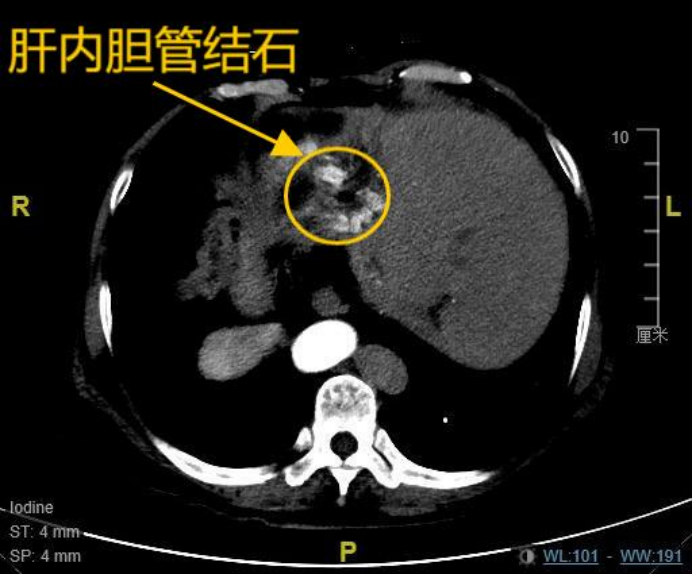

患者韩女士(化名),67岁,8年前因胆总管结石、胆囊结石曾接受传统开腹手术,术后三年结石复发,导致其长期饱受肝内胆管结石困扰,反复发作的右上腹疼痛严重影响了她的生活质量。更为特殊的是,韩女士存在罕见的全内脏反位,即医学上所指的“镜面人”,她的心脏、肝脏、脾脏等脏器均与正常解剖位置呈镜像反位分布,这是一种罕见的内脏解剖变异,发生概率约万分之一,这为手术操作带来极大挑战。8年前,由于特殊的身体情况,其开腹手术曾耗时长达10小时。近期复查的肝胆ct提示:肝内胆管多发结石伴肝左叶萎缩,肝总管及部分二级胆管扩张。面对多家医院“需再次开腹”的诊疗建议,患者坚持寻求微创尊龙凯时平台入口的解决方案,最终慕名求诊于哈医大一院肝脏微创外科麻勇主任团队。